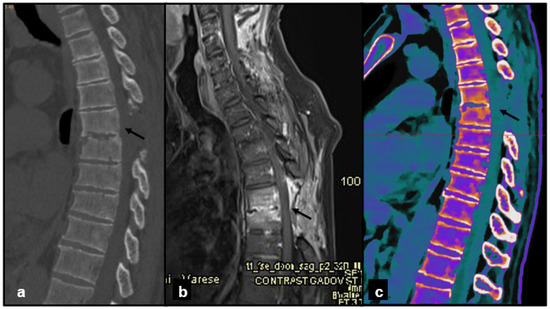

Figure 2. (a) Sagittal CT image, baseline acquisition of the thoracic spine, showing only the osteodense aspect of the vertebral body of D8 (black arrow). (b) Sagittal MRI acquisition with STIR sequence, clearly showing the hyperelectronicity of the D8 vertebral body, indicative of interstitial edema (white arrow) and an acute process. (c) Sagittal DL-SCT image, post-processed with IntelliSpace software, showing an increase in ED at the level of D8 vertebral body (orange color, black arrow), indicative of spongy edema. Color bar legend. White: normal cortical bone; orange: intermediate to high ED; purple: low ED; blue: very low ED, consistent with normal bone marrow composition rich in fat.